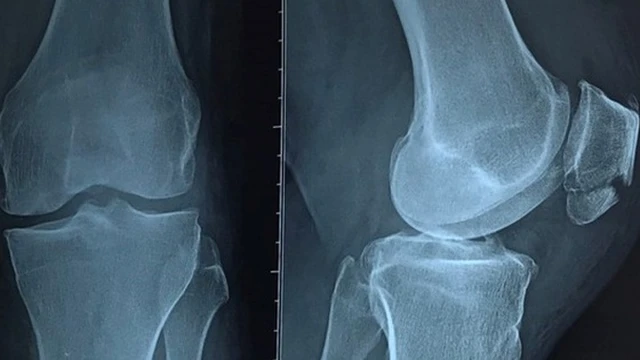

Gãy xương bánh chè thường gặp khi bệnh nhân ngã và khuỵu đầu gối xuống đất. Chấn thương này chiếm 2 - 4 % tổng số ca gãy xương. Vậy gãy xương bánh chè được định nghĩa như thế nào và làm sao để điều trị chấn thương này hiệu quả? Hãy đọc bài viết dưới đây của nhà thuốc Long Châu để tìm được câu trả lời nhé.